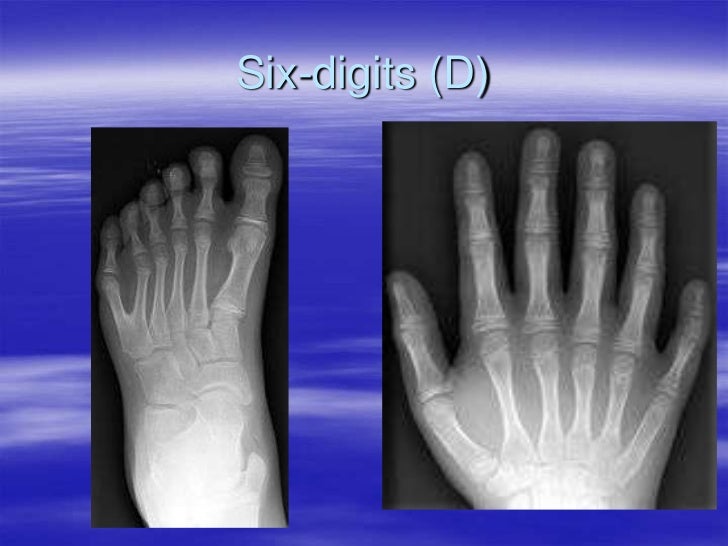

Polydactyly Interlocking Fingers Gene Syndactyly is one of the most common hereditary limb malformations depicting the fusion of certain fingers and/or toes. Without thinking about it, fold your hands together by interlocking your fingers. Observe which thumb is on top (right or left). One study found that 55% of people place their left thumb. Which thumb is on top—your left or your right? This. Interlocking Fingers Gene.

Frontiers Clinical of Polydactyly An Updated Review Interlocking Fingers Gene The three main interlocking developmental axis of the growing limb bud are the proximodistal, running in the human arm. Which thumb is on top—your left or your right? Observe which thumb is on top (right or left). Syndactyly is one of the most common hereditary limb malformations depicting the fusion of certain fingers and/or toes. Without thinking about it, fold. Interlocking Fingers Gene.